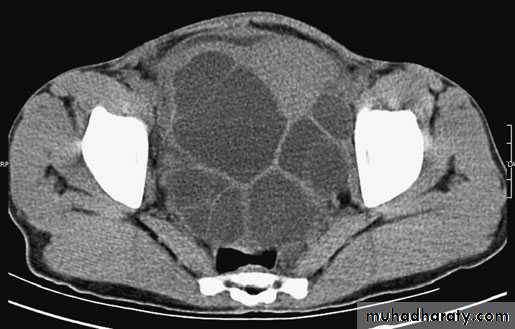

The liver is the organ most often affected. The lung is the nextmost common. The parasite can affect any organ or several organs in the same patient

Ultrasound and CT scan are the investigations of choice. The CT scan shows a smooth space-occupying lesion with several septa .An ultrasound of the biliary tract may show abnormality in thegall bladder and bile ducts. Hydatid infestation of the biliary system should then be suspected.